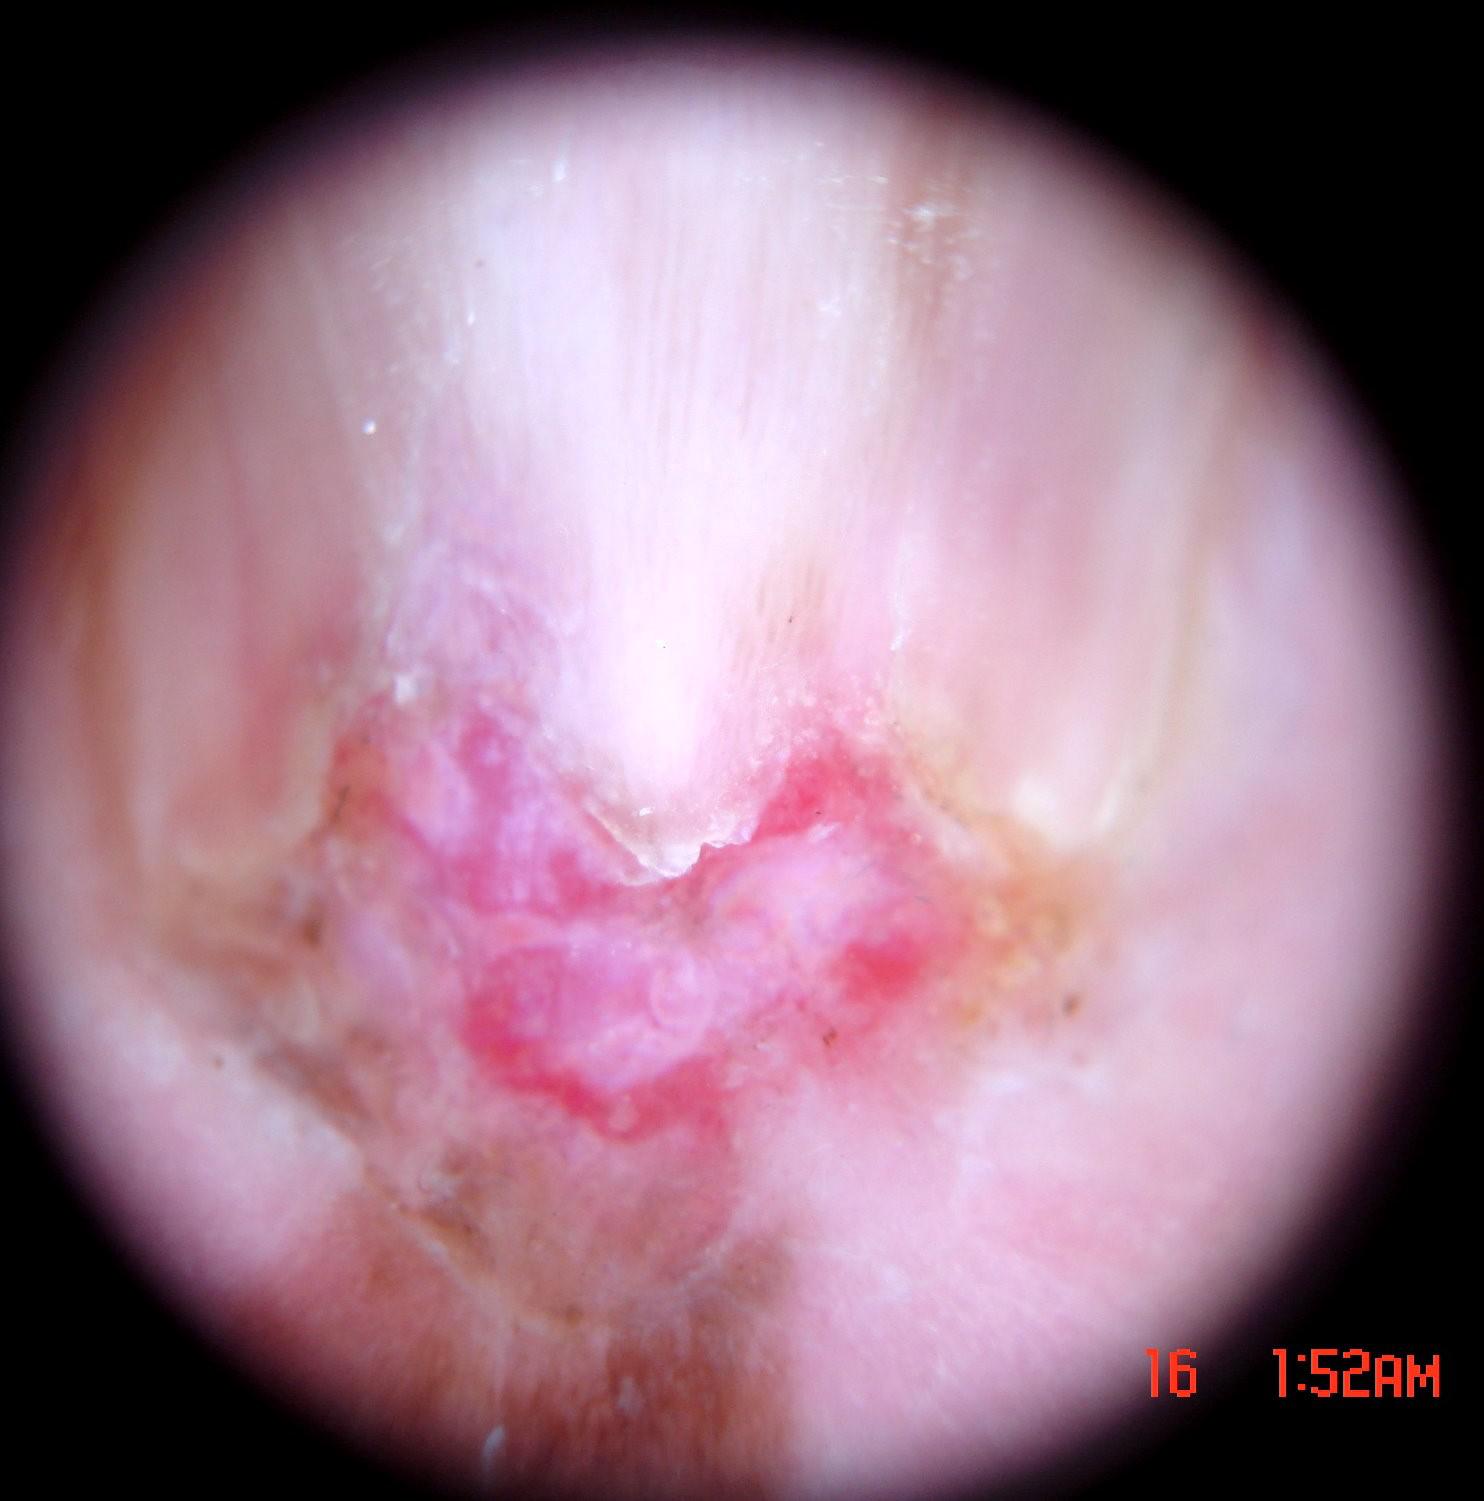

{

"age_approx": 65,

"anatom_site_general": "upper extremity",

"anatom_site_special": "acral NOS",

"concomitant_biopsy": true,

"dermoscopic_type": "non-contact polarized",

"diagnosis_1": "Malignant",

"diagnosis_2": "Malignant melanocytic proliferations (Melanoma)",

"diagnosis_3": "Melanoma in situ",

"diagnosis_confirm_type": "histopathology",

"family_hx_mm": false,

"image_type": "dermoscopic",

"mel_thick_mm": "0.00",

"melanocytic": true,

"patient_id": "IP_3069248",

"personal_hx_mm": false,

"sex": "male"

}